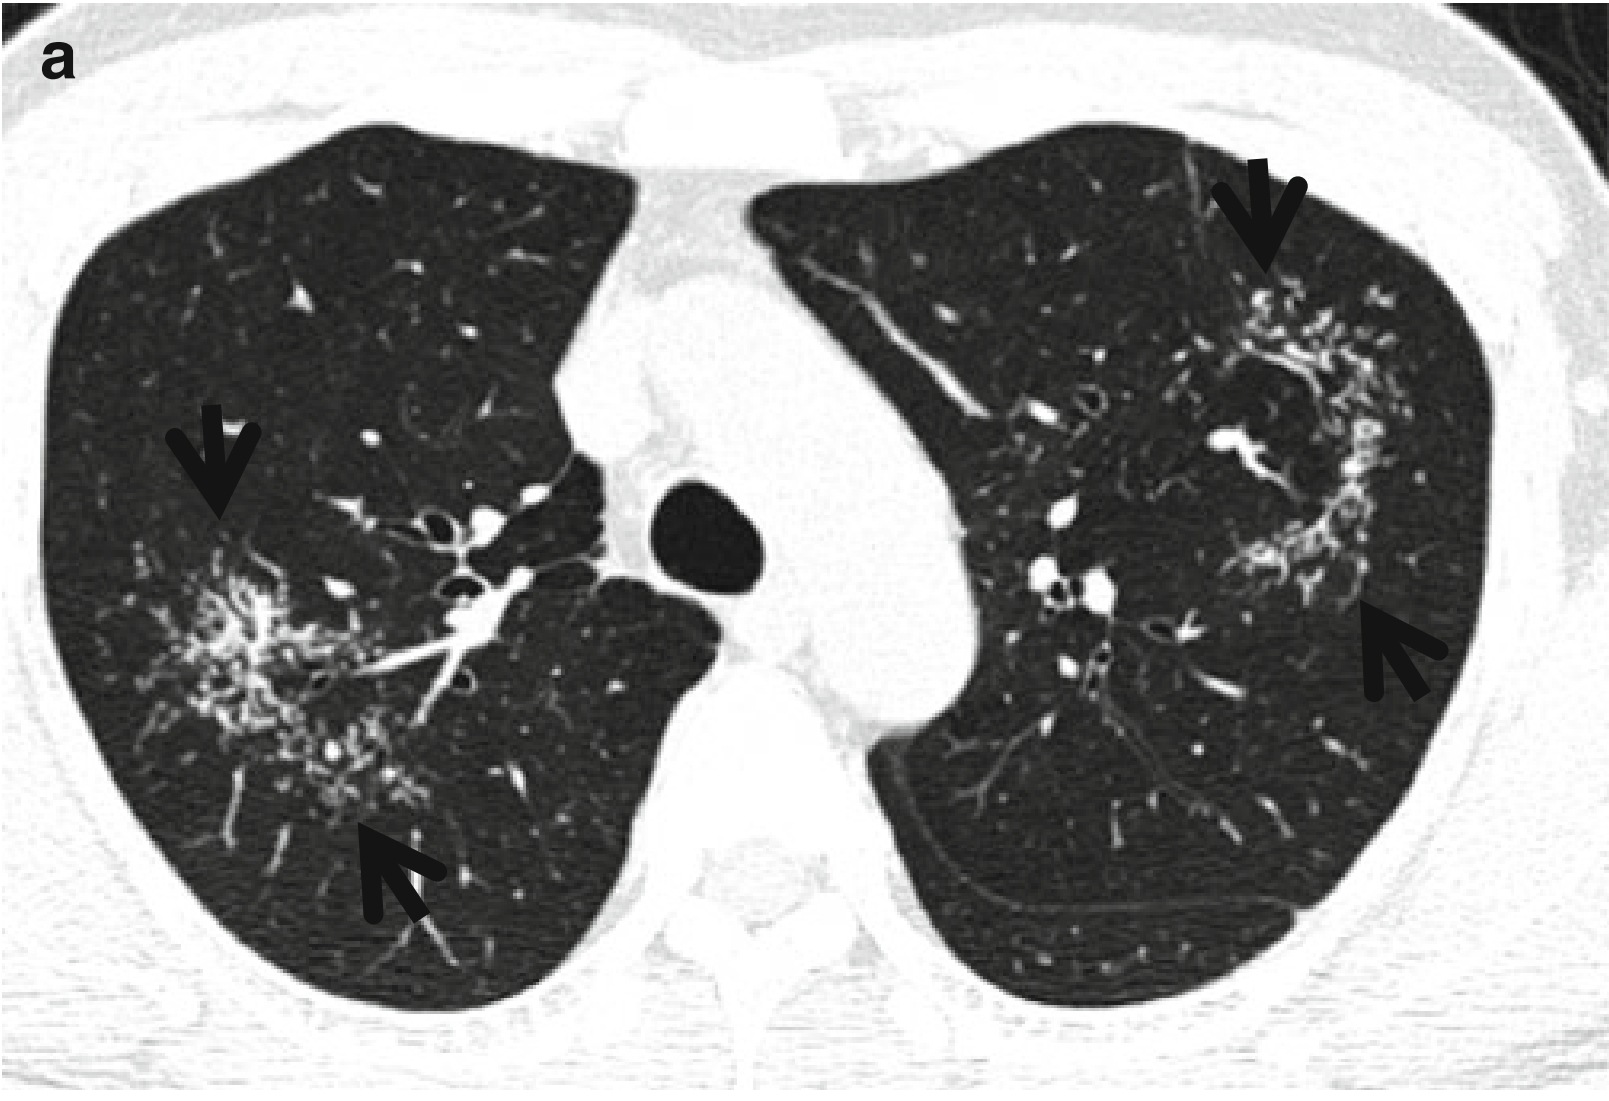

CT表现:CT表现为上叶和下叶背段簇状的单发或多发结节伴星系征,或星系征不伴有淋巴结肿大、树芽征,均支持肺结核的诊断,而非肺结节病(图2和图3)。

图3 CT星系征。男,53岁,活动性肺结核患者。薄层CT扫描(层厚=2.5mm)分别于主动脉弓水平(a)和奇静脉弓(b)水平肺窗示双肺上叶和左肺下叶背段的星系征(箭头所示)。

CT-病理对照:在 HRCT上,CT星系征反映了多发肉芽肿的聚结,越往簇中心肉芽肿越密集,当肉芽帅结合得不甚紧密时,光镜下可分辨单个的肉芽肿(图2)。